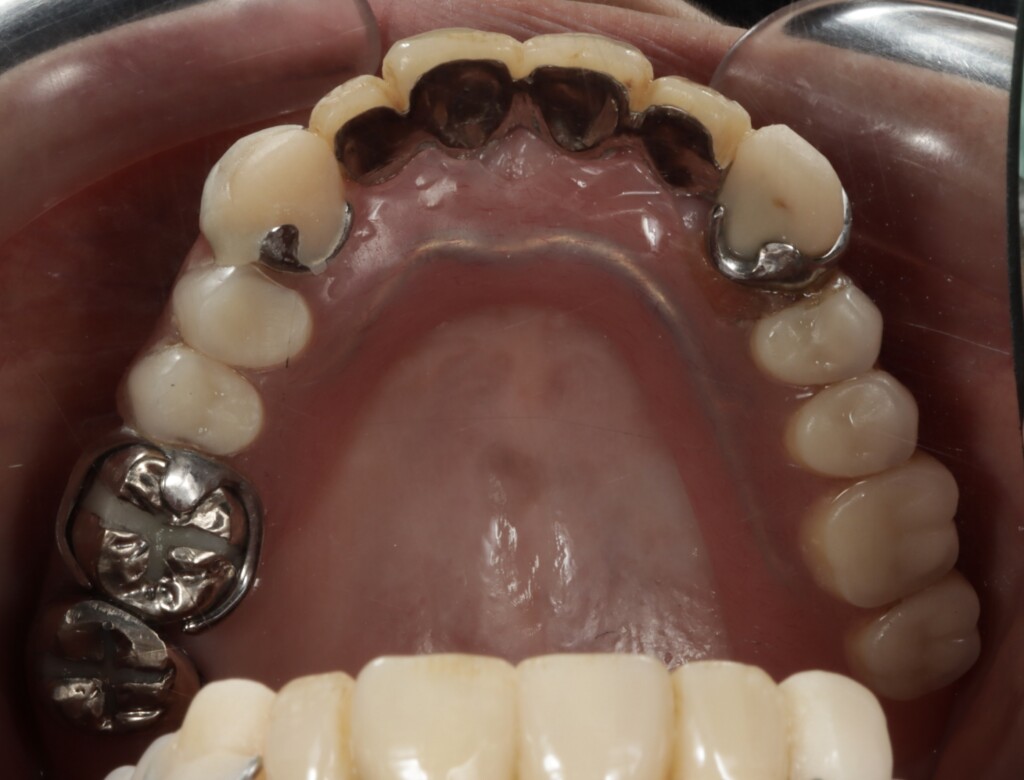

写真1:口腔内の正面観

*下顎は部分入れ歯を修理した総入れ歯が装着されている

写真4:上顎の状態

上顎は、前歯部にブリッジ、右上奥歯には銀の被せ物が装着されている状態でした。しかし、それらを支えているご自身の歯との境目から虫歯が進行しており、残っている歯のほぼすべてに問題が認められました。特に右上の前歯は、歯ぐきの下にまで虫歯が進行しており、汚れが溜まりやすい状態となっていたため、歯ぐきにも強い炎症がみられました。また、その他の歯についても、虫歯ではない健全な歯質が歯ぐきの縁付近までしか残っていない状態で、歯としての支える力が大きく低下していました。